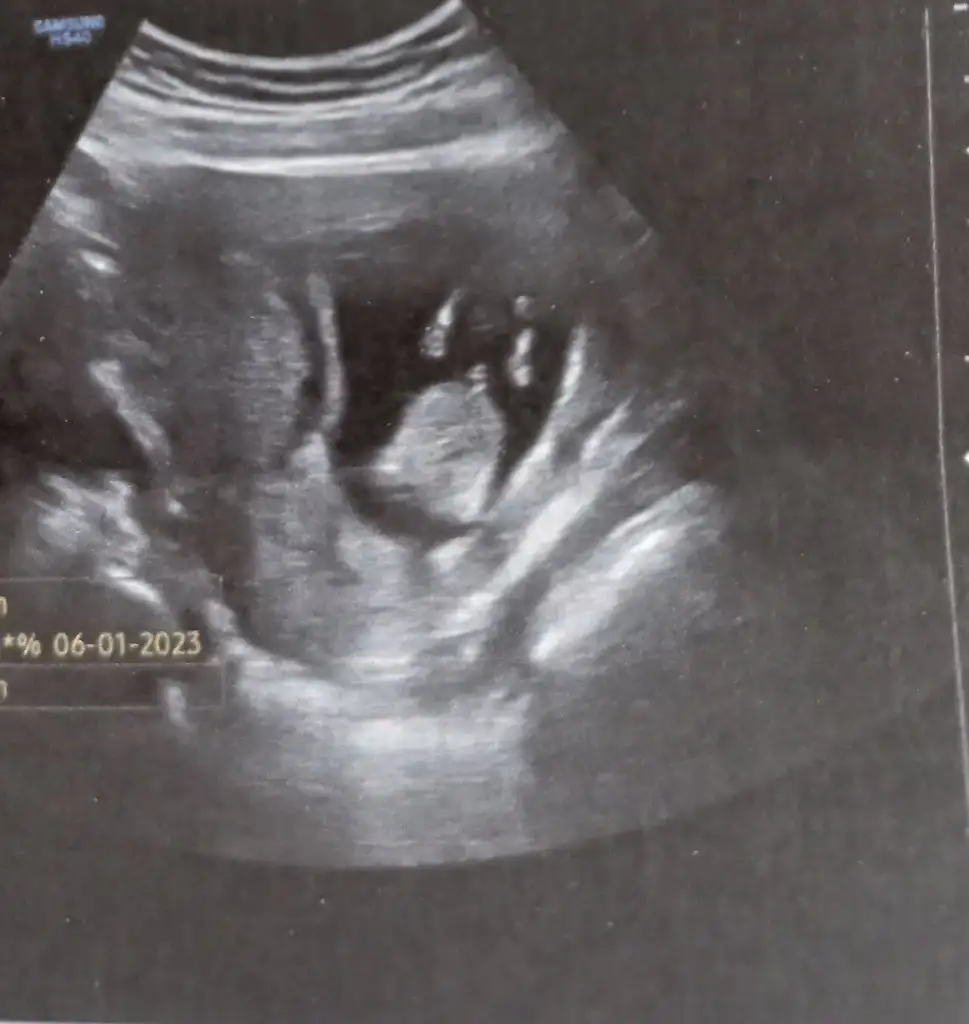

Valla bu zamana kadar hep kız dediler şimdi bariz gösteriyordu 100 de 100 erkek dedi ilk sağlıklı gebeliğim erkek annesi olmaktan korkuyorum ama hayırlı olsun gerisi önemli değil :)

Ay maşallah bak annesi nasıl sakince yatıyor. Hiç korkma canım erkekler gerçekten annelerine düşkün oluyor genelde. 6yasindaki oğlum prenses annem diye seviyor beni hiç kıyamaz bana ☺️ bende çocuklarıma gerçi hep saygı gösterip onemsedim çocuktur anlamaz demedim onu da çok etkisi var. Değer verilen çocuk değer vermeyi öğrenir. Ben senin annenim yerini bil moduna geçmedim hiç. Simdikinin kızıda erkegide hareketli oluyor zaten zamane çocukları oyuzden korkuyorsan da 😅